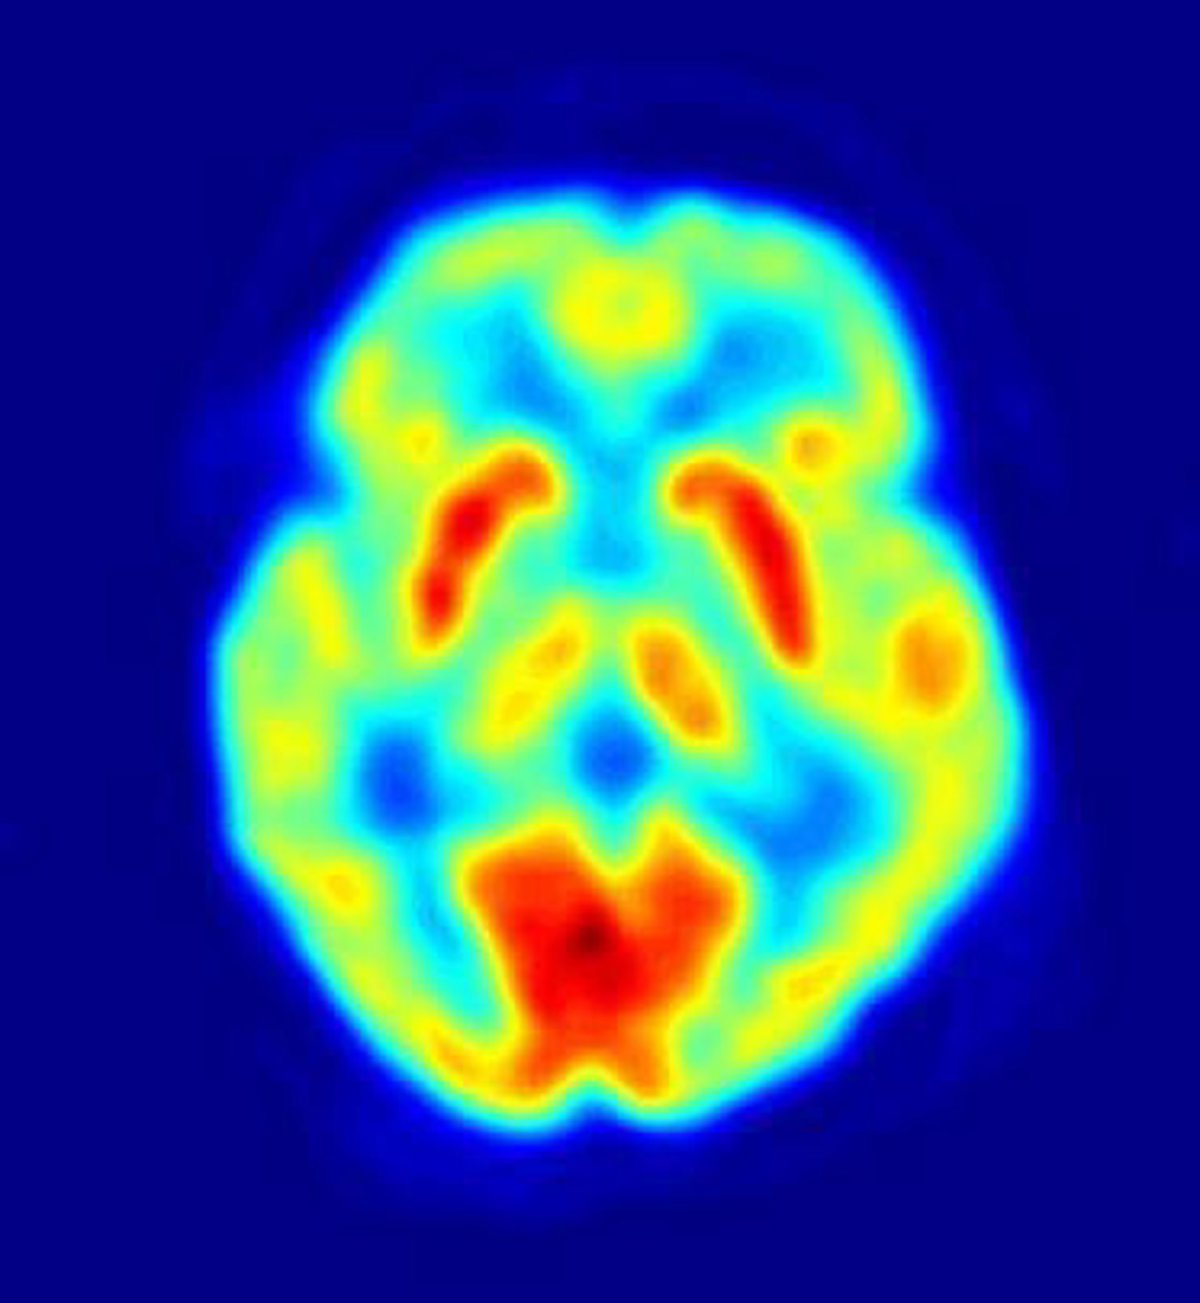

Según señalan los investigadores, las diferencias en la personalidad que surgen en relación a los sentimientos humanos de desigualdad modifican la actividad en la amígdala, una región cerebral importante para el procesamiento emocional automático. El estudio contradice ideas previas que sugieren que tales diferencias de personalidad se deben a diferencias en la corteza prefrontal.

Los investigadores descubrieron que la actividad en la amígdala difería entre estos dos grupos de personas y que la mayor recompensa desigual se asociaba con una mayor actividad de la amígdala en las personas prosociales. Por ello concluyen que la característica aversión prosocial a la desigualdad está vinculada a la actividad en la amígdala y no depende del control consciente de los impulsos egoístas.